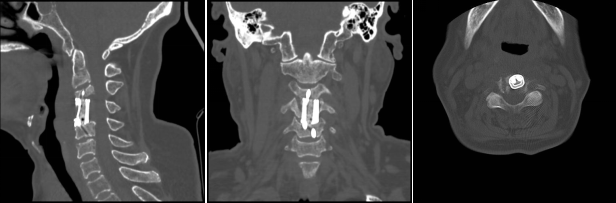

術(shù)后影像學顯示,植入內(nèi)植物位置滿意,與終板匹配性良好,穩(wěn)定性佳。術(shù)后患者生命體征平穩(wěn),癥狀明顯緩解,活動良好,目前已出院。

通訊員殷君發(fā)報道:近日,衡陽市中心醫(yī)院脊柱外科蘇光輝主任團隊順利完成一例高難度頸椎骨質(zhì)破壞病灶切除+3D打印一體式椎體植入重建手術(shù),術(shù)后影像學顯示,植入內(nèi)植物位置滿意,與終板匹配性良好,穩(wěn)定性佳。術(shù)后患者生命體征平穩(wěn),癥狀明顯緩解,活動良好,目前已出院。此手術(shù)的圓滿成功是衡陽市中心醫(yī)院3D打印技術(shù)臨床應用領(lǐng)域取得的又一重要突破,是湘南地區(qū)乃至全省首例疑難病癥的創(chuàng)新舉措,標志著脊柱外科手術(shù)開始邁向個性化、精準化。